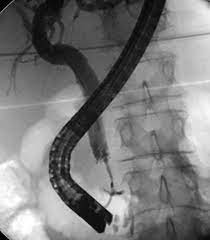

- Endoscopic Retrograde Cholangiopancreatography (ERCP): A procedure that uses a camera to examine the bile ducts and take tissue samples for testing.